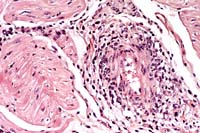

- Contributor's Diagnosis and Comments: Heart: Moderate

subacute perivasculitis and vasculitis. Mild multifocal subacute

myocarditis. Lung: Severe chronic bronchointerstitial pneumonia

with bronchiectasia and bronchiolitis obliterans (not submitted).

- The heart is submitted for Wednesday Slide Conference. The

perivascular region and the vessel walls are infiltrated with

mononuclear inflammatory cells. The endothelial cells are activated,

and in some regions there is a hyaline degeneration of the vessel

wall. This vasculitis was seen in the brain, intestine (vessels

of the submucosa), and the heart.

- Case 5-1. Heart: Note moderate influx of lymphocytes,

few histiocytes, and rare neutrophils within and around the vessel

wall.

AFIP Diagnosis: Heart, myocardium: Vasculitis and perivasculitis,

lymphohistiocytic and plasmacytic, multifocal, moderate, with

vascular fibrinoid necrosis, mild interstitial edema, and myocardial

necrosis, Brown Swiss, bovine.